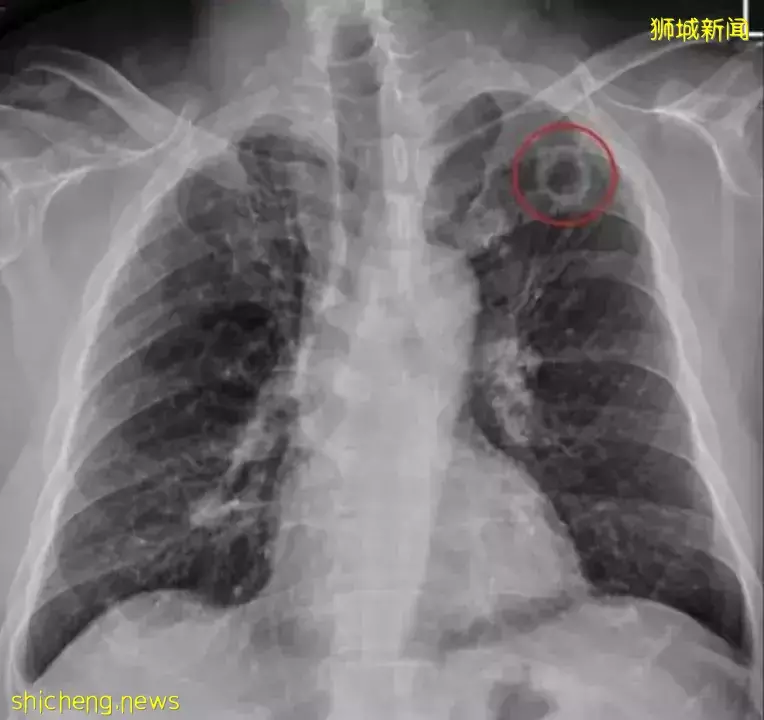

没想到,却惊悚发现自己其实感染了肺结核,X光检查出左上肺有一个2.5公分的破洞......

据医院官方通告,这个56岁卢姓男子的痰液抹片结核菌为阴性。但电脑断层扫描判定左上肺破洞为肺结核菌所造成。

目前这个病人正在接受抗结核药物治疗,治疗进展未知。